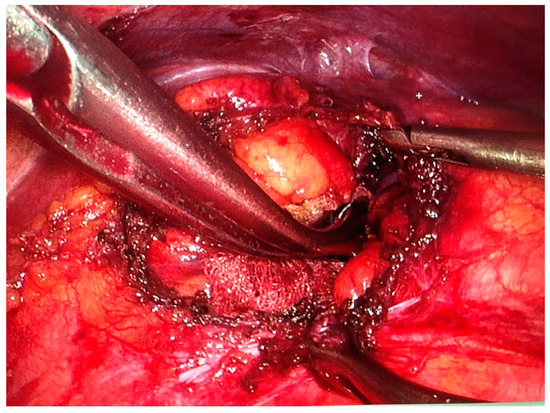

Figure 4.

Herniorrhaphy of the diaphragm before the application of the mesh.